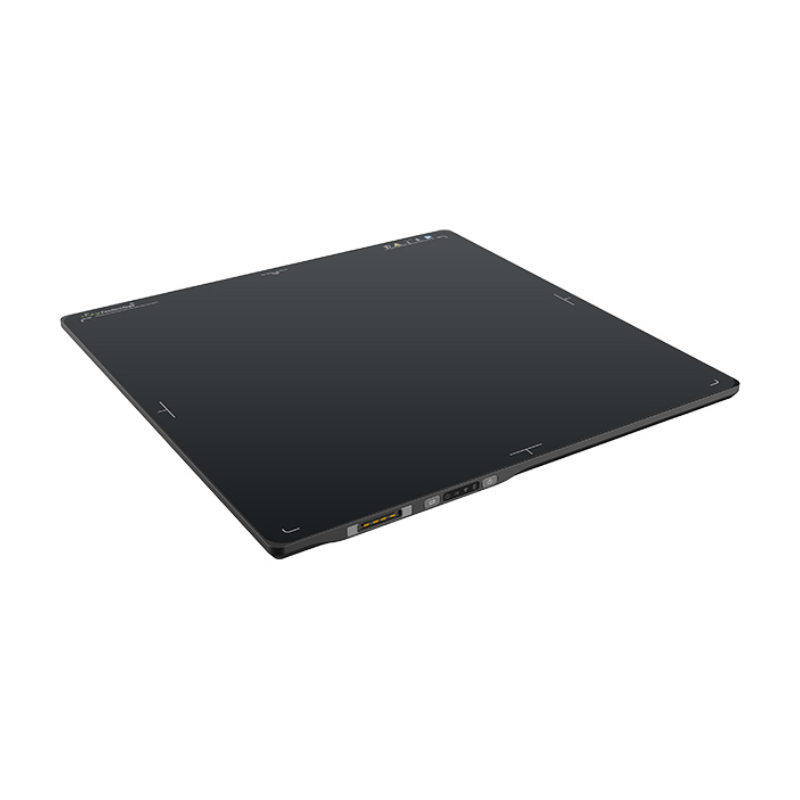

X Ray

What are medical x-rays?X-rays are a form of electromagnetic radiation, similar to visible light. Unlike light, however, x-rays have higher energy and can pass through most objects, including the body. Medical x-rays are used to generate images of tissues and structures inside the body. If x-rays traveling through the body also pass through an x-ray detector on the other side of the patient, an image will be formed that represents the “shadows” formed by the objects inside of the body.